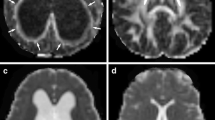

Each group of animals exhibited considerable ventriculomegaly throughout the study period (Fig. 1; see also [42]) that was accompanied by significant changes in various white matter regions (Fig. 2; Table 1). No significant differences were noted between the right and left sides of the optic chiasm, optic tract, or internal capsule, and therefore left and right data points for each of these regions were pooled.

Representative MRI/DTI from early group prereservoir treatment demonstrating white matter regions of interest in DTI (a, d, g), tractography color maps (b, e, h), and T2-weighted images (c, f, i). The corpus callosum (CC) is thinned when the ventricles are dilated but is detectable on DTI at this early stage: fibers from the CC are seen on the color map as red/purple, indicating lateral crossing fibers. These fibers are lost on MRI/DTI and color maps after 3 weeks of reservoir treatment. The fibers of the internal capsule (IC) run in the anterior–posterior direction as well as superior–inferior and are seen as green on color maps. The IC is medial (a) and posterior (d, g) to the optic tract (OT), which runs anterior and lateral from the optic chiasm (OC) to the lateral nucleus of the thalamus. Fibers of the OC are also seen as red/purple because of their lateral crossing nature. The external capsule (EC) is stretched along the outer wall of the lateral ventricle (LV) and is one of the first structures lost with progressive hydrocephalus. 3rd V Third ventricle